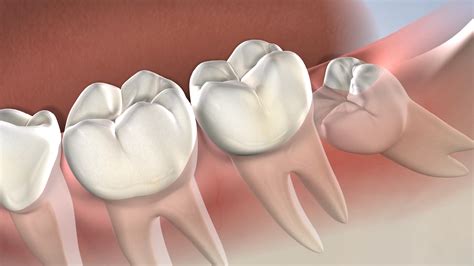

Experiencing sudden, excruciating pain in the back of your mouth is an experience few forget. While mild discomfort might sometimes be managed with home remedies, there are moments when you require the emergency removal of wisdom tooth procedures to prevent severe complications. Understanding when a situation has escalated from routine dental care to an urgent medical necessity can save you from prolonged agony and serious health risks. Wisdom teeth, or third molars, are notorious for causing trouble because there is often not enough room in the adult jaw for them to emerge properly, leading to impaction, infection, and damage to adjacent teeth.

The primary reason for the emergency removal of wisdom tooth is often pericoronitis—an infection of the soft tissue surrounding a partially erupted tooth. When a wisdom tooth only partially breaks through the gum, it creates a small flap of tissue (operculum) where food particles and bacteria can easily become trapped. This area is notoriously difficult to clean, leading to infection.